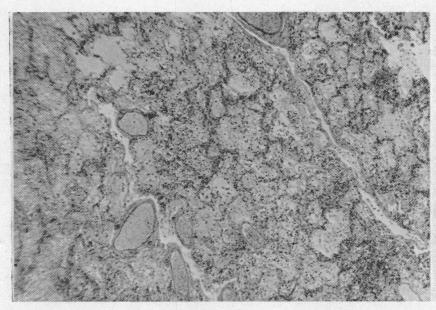

Further studies of high altitude pulmonary oedema.

Br Heart J. 1962 Jan;24(1):95-102. doi: 10.1136/hrt.24.1.95.